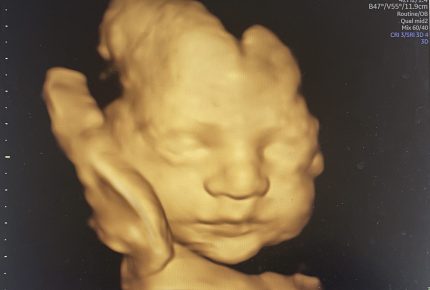

24-32+ weeks 4D Scan

If you just cannot wait until baby is born to find out whether they will have Dad’s nose or Mum’s chin then either of our Can’t Wait to Hold You packages are the perfect choice. Suitable from 24-32 weeks. After 32 weeks may be a challenge as baby has a bit less room in there and gets ready to make its entrance!

• Viewing your baby in HD 4D live during the scan which is a live motion video of baby in your bump

• View your baby in HD 4D live during the scan which is a live motion video of baby in your bump